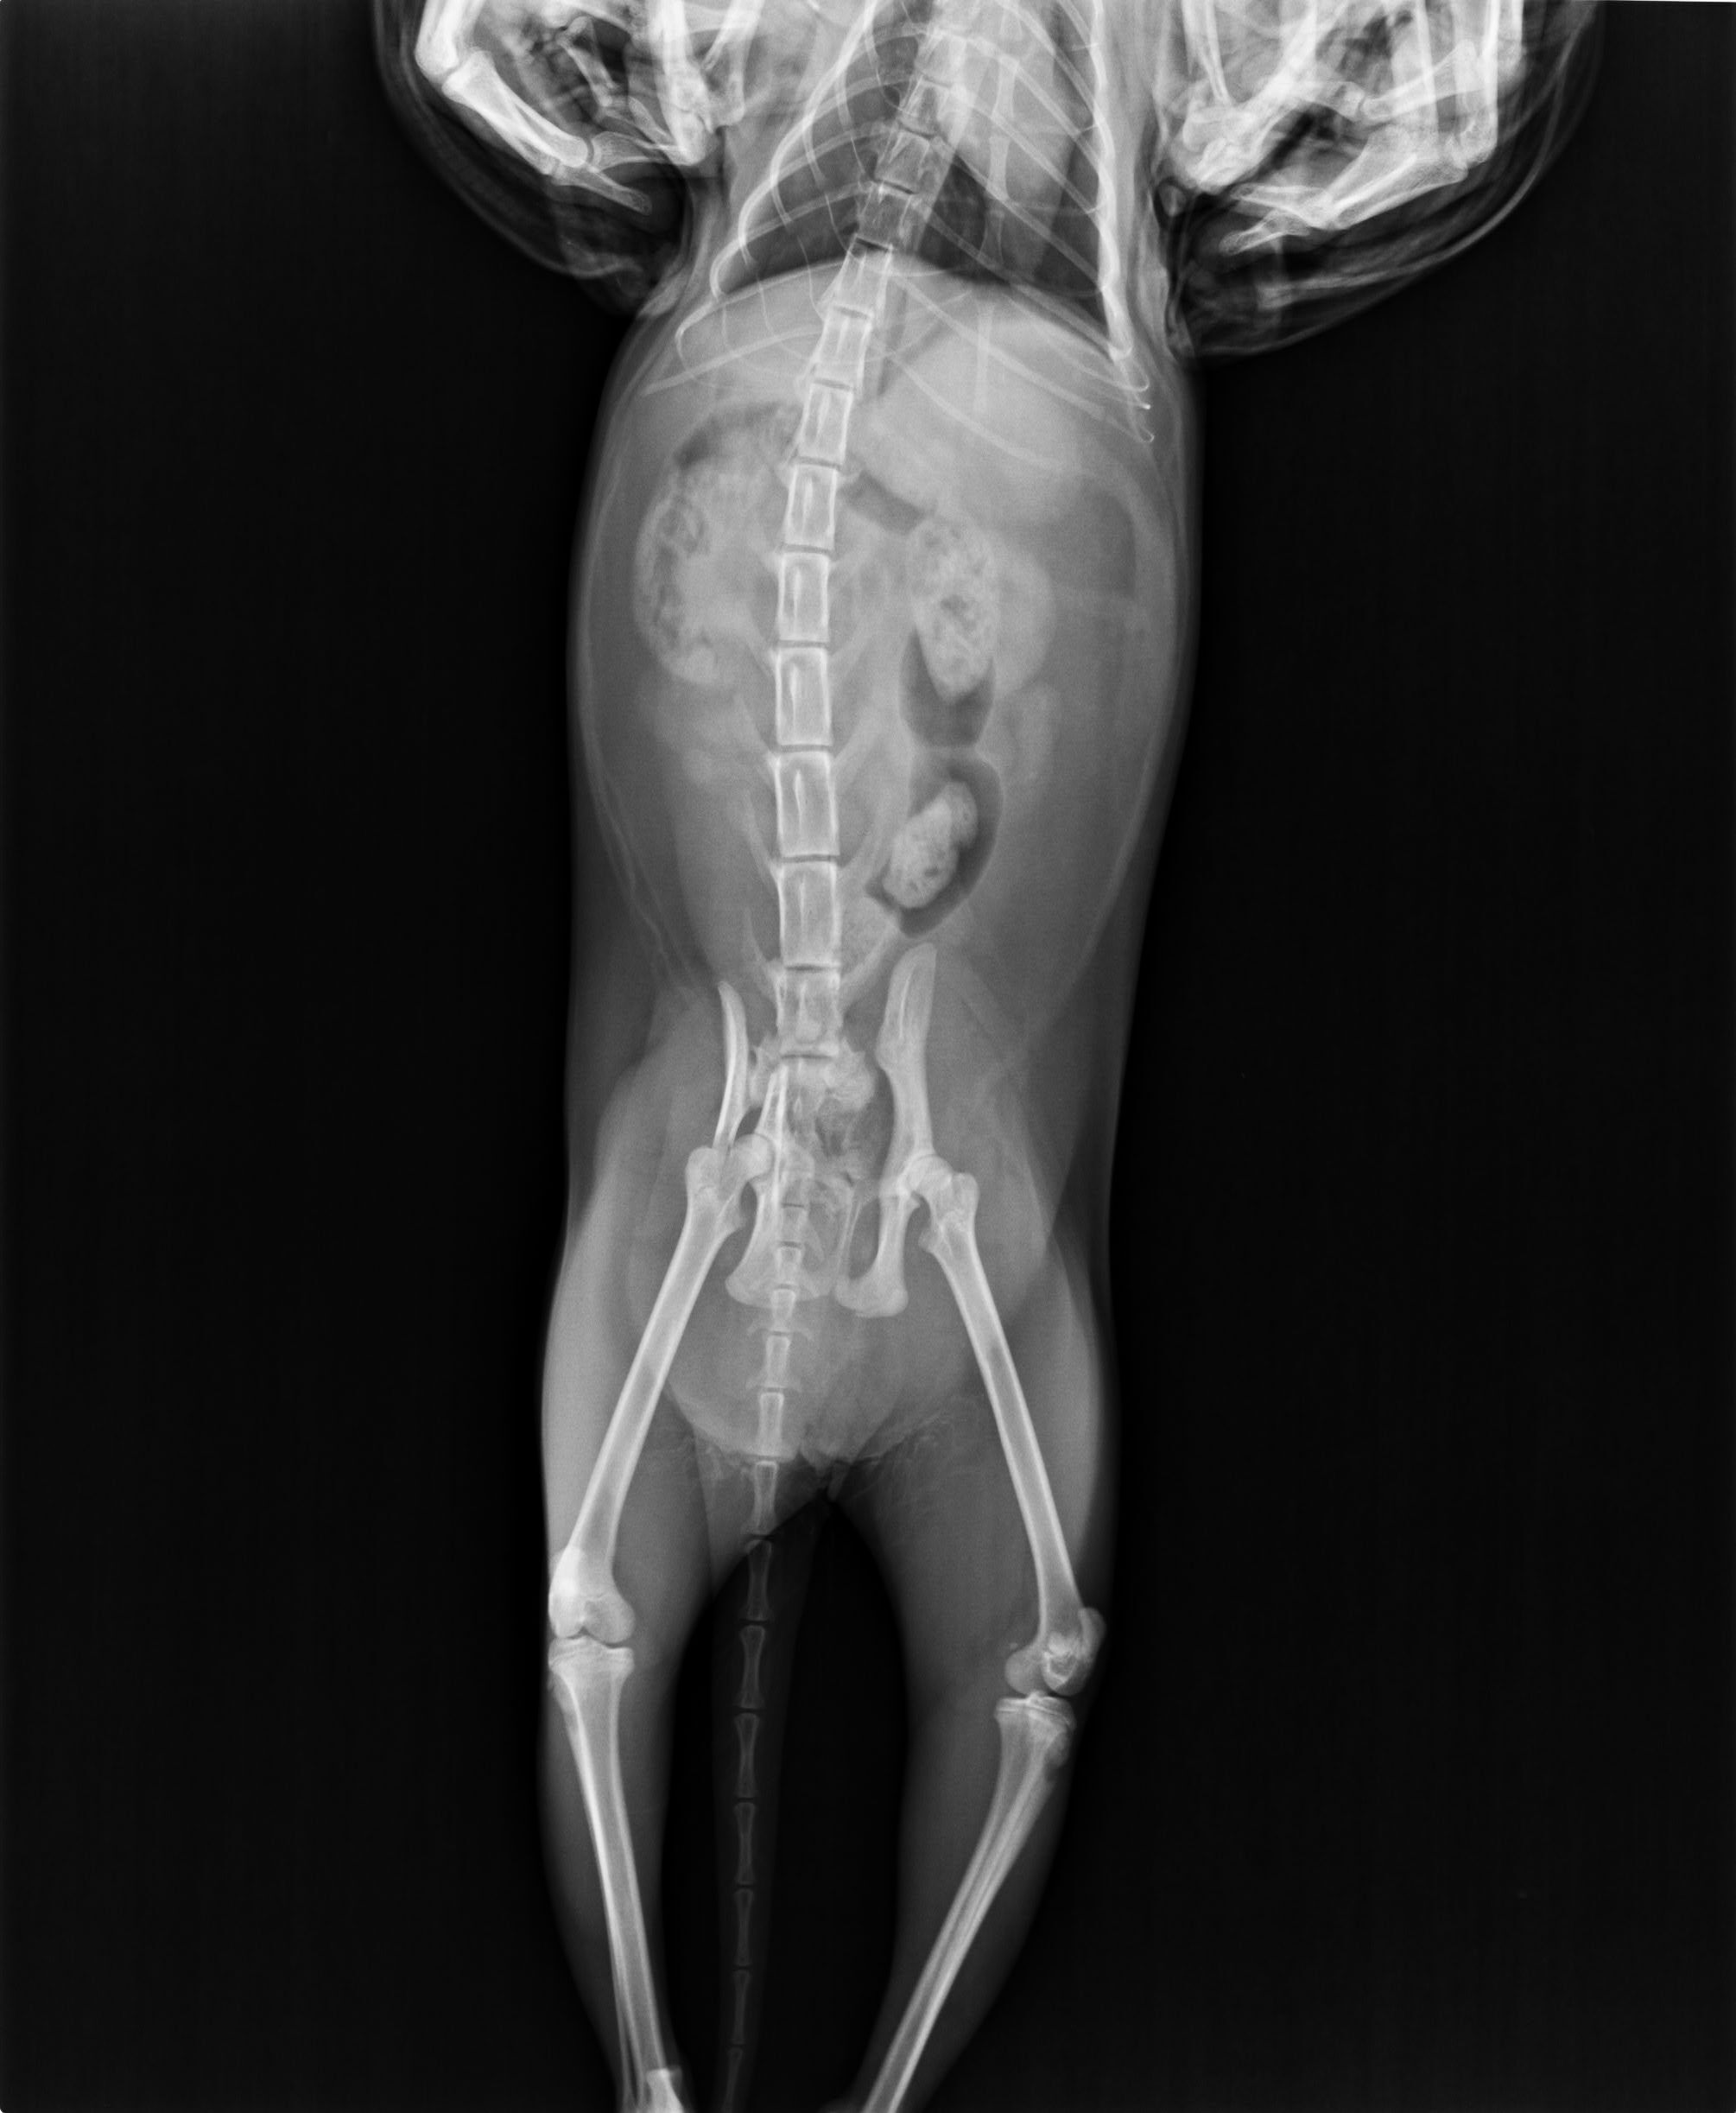

主題: 車禍骨折的三花貓 申請者姓名: 黃儀芬 花色: 申請日期: 2013-04-19 12:50:53 申請者部落格: 申請者臉書網址: 所在縣市/合作醫院: 台北市/其他院所醫助專案(醫院請先MAIL溝通) 治療費用: 20000元 需求人數: 41人 已結案 (2013-06-27 14:24:14) 報名人員: Ocean x2(已付款)、茶咪(已付款)、茶咪、Irene Chen x2(已付款)、Yu Chung(已付款)、茶咪、lavinia(已付款)、小筑Q醬 x2(已付款)、vivian(已付款)、洪嘉淑 x2(已付款)、張湘婷、謝小欣(已付款)、Hllen Liu(已付款)、beforn x4(已付款)、p.p(已付款)、Amy Chou x2(已付款)、Kim Meng(已付款)、Jessica Hsu(已付款)、Kate(已付款)、林紫翠 x2(已付款)、小豬(已付款)、Emily Chou x10(已付款)、Sunny Chen(已付款)、Den Miyako x2(已付款)、Sandy Shen(已付款)、 候補人員: 動物病情說明: 3/14貓咪被發現在我們店後面的紙箱堆中,疑似遭到車禍撞擊緊急送醫。3/14晚間先安排貓咪住院穩定其生命跡象,3/15再送往醫師建議的美國愛屋動物醫院。

由於骨折及神經修復有時效性,故安排於3/16動手術。

我們有請醫院開立估價單,原價為72600~72800,但因為是浪浪救援,醫院為我們打折,手術加住院總金額為4萬元整。可是還是超過了我們所能負擔的範圍.....希望能透過協會的力量幫我們湊齊不足的醫藥費用....動物近況說明: 貓咪由原本需要醫師幫忙擠尿擠便進步到可以自行如廁,左後腿恢復良好,右後腿小腿以下無明顯反應走路腳掌會拖行,目前持續復健中。